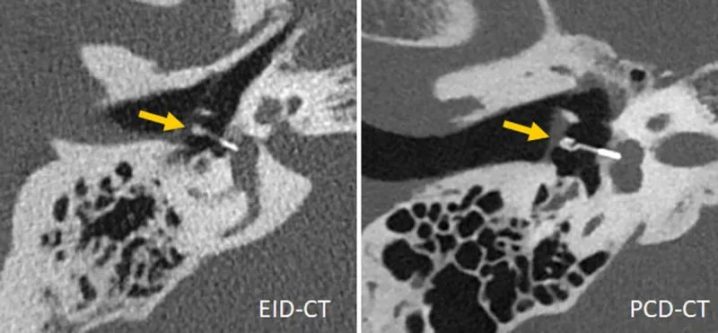

最近,在一项对5具尸体头部的研究表明,与EID-CT相比,PCD-CT在颞骨的超高分辨率(UHR)检查中提供了优越的图像质量和显著的剂量节省(平均剂量减少79.3%)。在13名患者的颞骨检查中,PCD-CT在评估所有个体解剖结构时被评为优于EID-CT,平均辐射剂量比EID-CT低31%。图6显示了一个临床案例,说明PCD-CT在内耳成像中的潜力。在使用小鼠作为样本对PCD-CT和EID-CT之间的最小骨骼细节的可视化进行比较时,发现在剂量匹配扫描中,PCD-CT比EID-CT提供了明显更小的图像噪声、更高的信噪比和更高的边缘清晰度。在骨小梁成像中,PCD-CT的有效容积空间分辨率(定义为每mm3可单独表示的元素数量)比传统CT高5倍以上。

图6 用第三代DSCT(左)和第一代PCD-DSCT采集的内耳扫描(右),显示PCD-CT对钛K活塞镫骨假体(箭头,远端直径0.4mm)的可视化效果更佳。